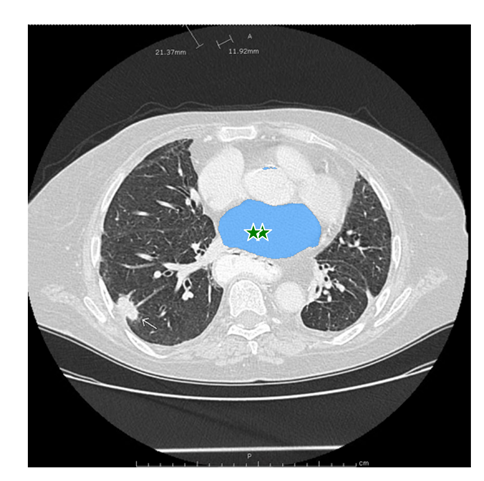

医学图像:

该图片是测试图片,从网站上下载的。